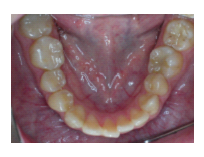

43歲女性病人,如圖1A所示。病人由其他醫師轉診來拔除左下顎嚴重蛀牙的第二大臼齒與阻生智齒,理論上如果拔除此第二大臼齒後,必須以人工植牙重建之,但是病人有經濟上的考量,因此與病人討論過後,決定將同時欲拔除的 阻生智齒移植入第二大臼齒齒槽,雖然病人年紀稍大,仍值得一試,圖1B 是術後一個月的X光片,由於病人年紀較大,智齒在植入缺牙區域時,已同時作根管治療,圖1C是術後四個月的X光片,根管內充填的是Vitapex(Ca(OH)2),圖1D是術後一年四個月後的X光片,智齒牙根尖的骨頭已經全部再生回來,而且牙根無黏連的情形,臨床上牙齒動搖度小於1,牙周組織健康,而其前面的第一大臼齒情況良好,咬合正常。

圖1A